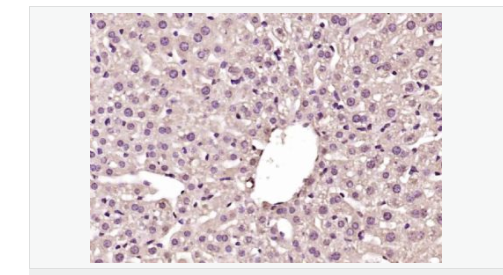

| 產(chǎn)品應用 | WB=1:500-2000 ELISA=1:5000-10000 IHC-P=1:100-500 IHC-F=1:100-500 IF=1:100-500 (石蠟切片需做抗原修復) not yet tested in other applications. optimal dilutions/concentrations should be determined by the end user. |